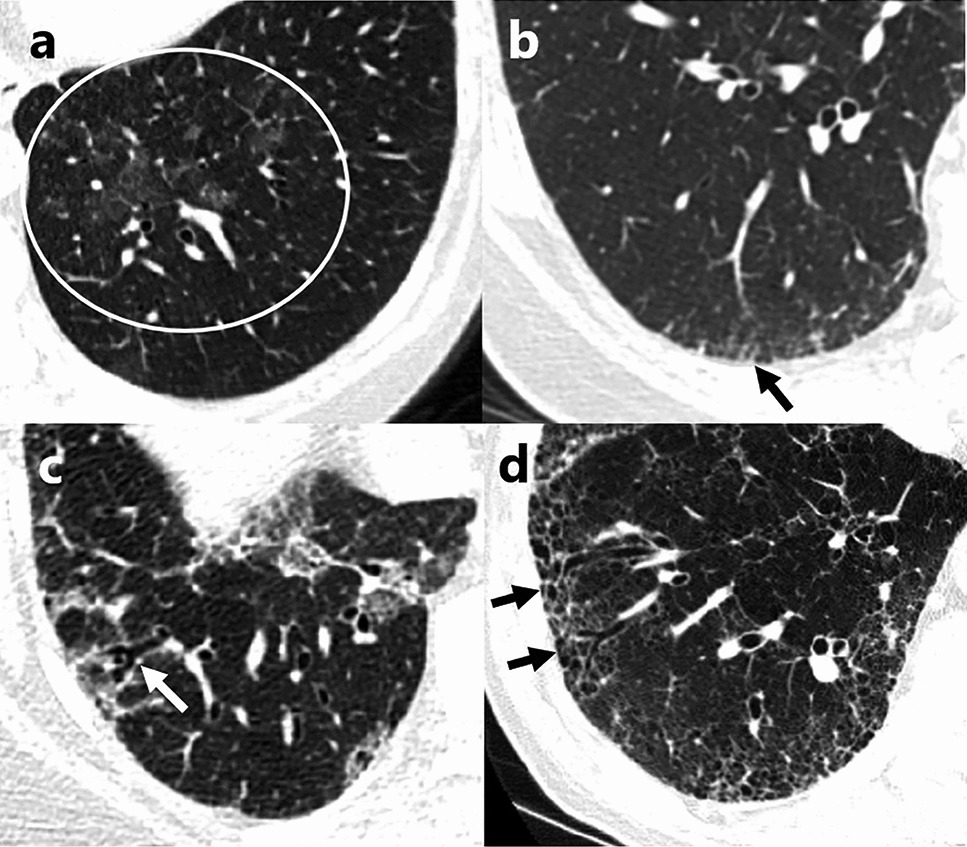

Cystic Lung Diseases: A Radiology Primer

Cystic Lung Diseases (CLD) represent a diverse group of lung diseases characterized by the presence of intraparenchymal cy...

Current Pulmonology Reports